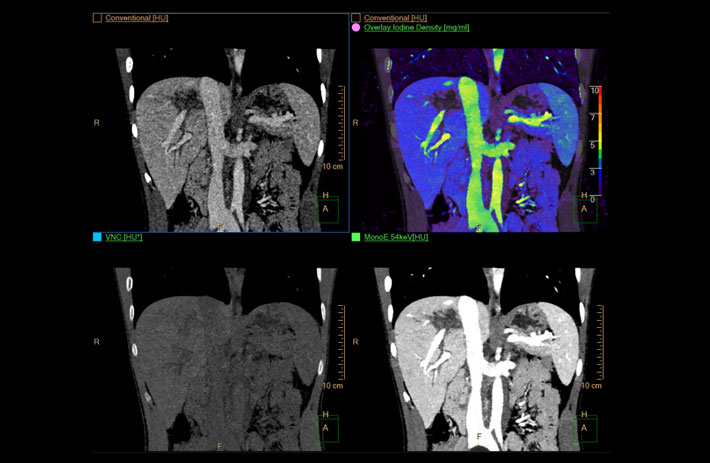

Mit dem Spektral-Detektor-CT werden Spektraldaten automatisch bei jedem Scan erfasst. Die Informationen stehen jederzeit auf der Scankonsole, der CT-Workstation sowie an jedem PACS-Arbeitsplatz zur Verfügung, sodass es nicht notwendig ist, den Patienten erneut zu scannen, bspw. wenn initial zufällige Anomalien festgestellt wurden. Dadurch profitieren Anwender durch eine höhere Diagnosesicherheit und weniger Nachuntersuchungen auf anderen bildgebenden Systemen. Unsere Fallsammlung zeigt, welchen klinischen Mehrwert der Spektral-Detektor-CT in unterschiedlichsten Anwendungsbereichen in der klinischen Routine bringt. Jede Woche gehen neue Fälle live.